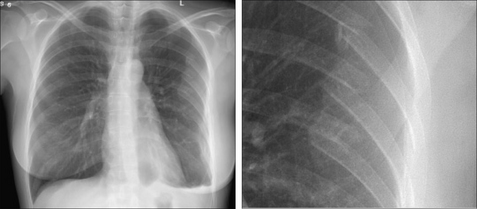

image

Figure 27.2 Female, 38 years. Chest pain. Silhouette sign...pneumonia in the lingular segments of the left upper lobe.